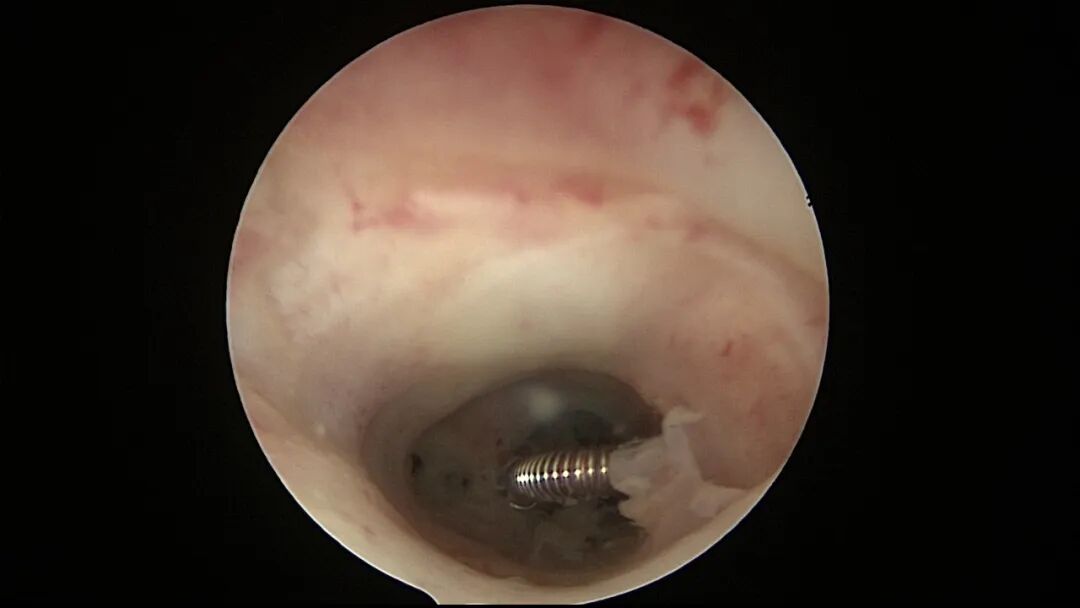

第八次宫腔镜:2025年7月宫腔镜二探取球囊,宫腔形态正常,双侧输卵管开口可见,内膜薄,片状充血。球囊在宫腔具有持续塑形作用,分粘术中没有显露的右侧输卵管开口已自我修复。